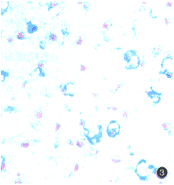

体外培养至第2周时,组织切片可观察到软骨组织样结构。至第3周时,软骨结构发育趋于成熟,HE染色见软骨细胞呈圆形,位于软骨陷窝内,表层组织内细胞密度较大,由表层至深层,细胞数量逐渐减少,软骨囊增大,排列欠规整(图2);阿新蓝染色可见基质蓝染,软骨陷窝清楚,陷窝周围有着色较深的软骨囊,囊间基质着色较浅(图3)。第3~16周,经离心管培养的软骨细胞保持软骨组织基本结构。第4、8、12和16周分别行钙染色,均未见软骨组织钙化现象。

图2 离心管培养第3周,细胞呈圆形,位于软骨陷窝内,表层细胞密度较大,深层细胞密度减少,软骨囊增大,排列欠规整HE染色×100

图3 离心管培养第3周,软骨基质呈蓝色,软骨囊、软骨陷窝清晰可见AB染色×400